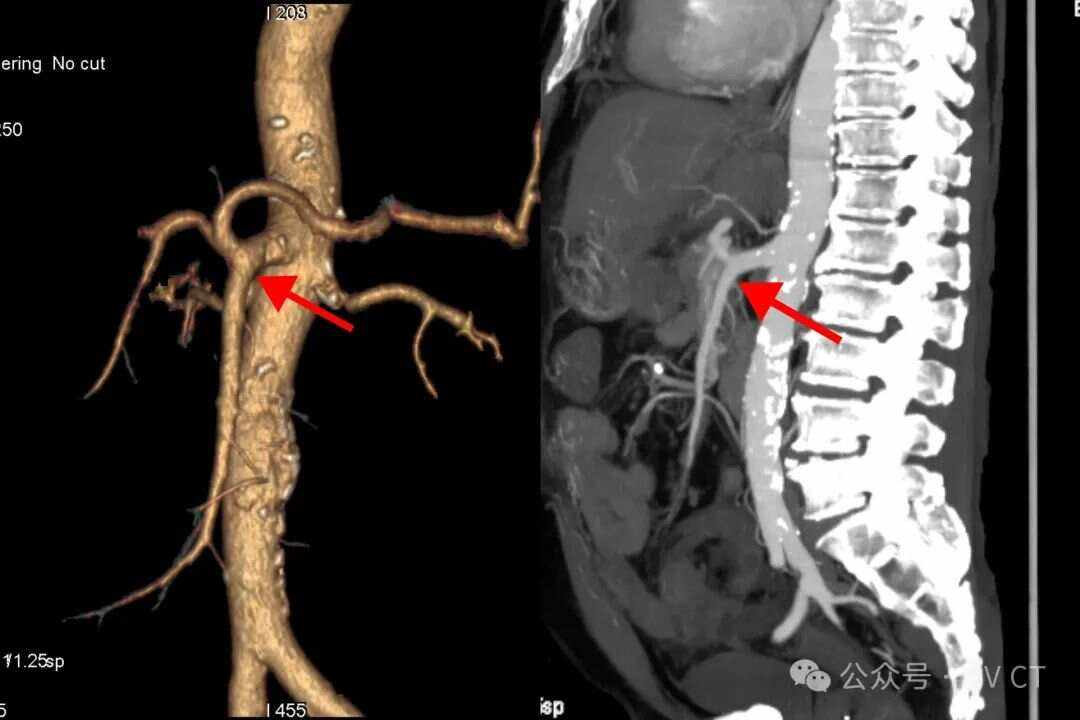

肠系膜上动脉压迫综合征是由于肠系膜上动脉压迫十二指肠水平部引发的一系列临床症状病因方面主要分为解剖因素和其他因素解剖因素表现为肠系膜上动脉与腹主动脉之间的夹角较小,导致十二指肠水平部受压其他因素包括消瘦肠系膜上动脉起始部粥样硬化以及内脏下垂等,这些因素可能通过改变血管位置或局部解剖。

肠系膜上动脉压迫综合征是指由于肠系膜上动脉或其分支压迫到十二指肠部分部位,引起十二指肠慢性淤积,导致十二指肠部分或完全阻塞梗阻的病症以下是关于肠系膜上动脉压迫综合征的详细解释1 病因与发病机理 主要由于肠系膜上动脉或其分支与十二指肠之间的解剖关系异常,导致动脉对十二指肠产生压迫 这种。